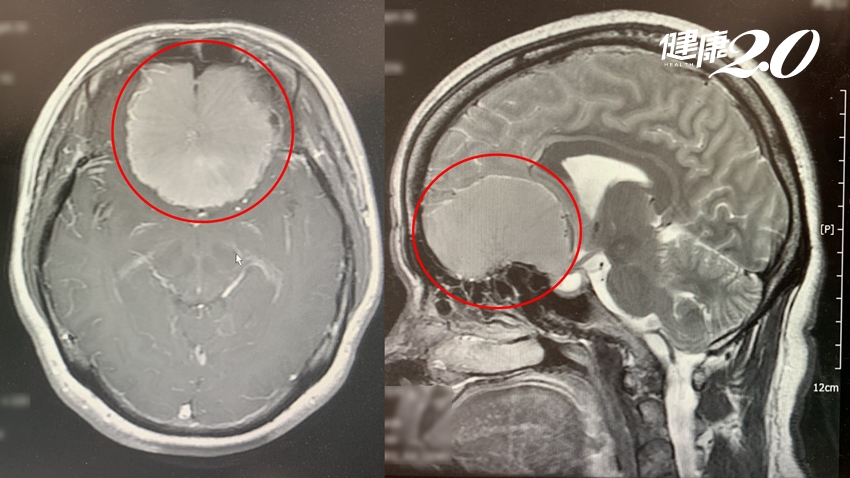

▲ 腦部電腦斷層掃描圖顯示,吳女士的腦部有一顆6到7公分的嗅溝腦膜瘤。

「終於聞得到我最喜歡的水果味了!」50歲的吳女士開心說出心裡話。2年多來,她幾乎沒有嗅覺,原以為是嚴重的過敏性鼻炎,直到視力也開始模糊,才就醫詳細檢查,發現竟是腦部長了一顆6到7公分的腫瘤,診斷為「嗅溝腦膜瘤」;緊急手術並住院2周後,終於找回正常嗅覺。

吳女士的腦腫瘤屬於「嗅溝腦膜瘤」,通常會長在前顱窩底篩板及其後方;可分為單側或雙側,單側較多見,也可能一側腫瘤為主,再向對側延伸。黃國烽說明,嗅溝腦膜瘤的早期症狀是逐漸失去嗅覺;若單側無嗅覺,則可判斷腫瘤位置在單側,但單側嗅覺障礙很容易被忽略;如果腫瘤已橫跨兩側,雙側嗅覺都會喪失,但又容易和過敏性鼻炎症狀混淆。